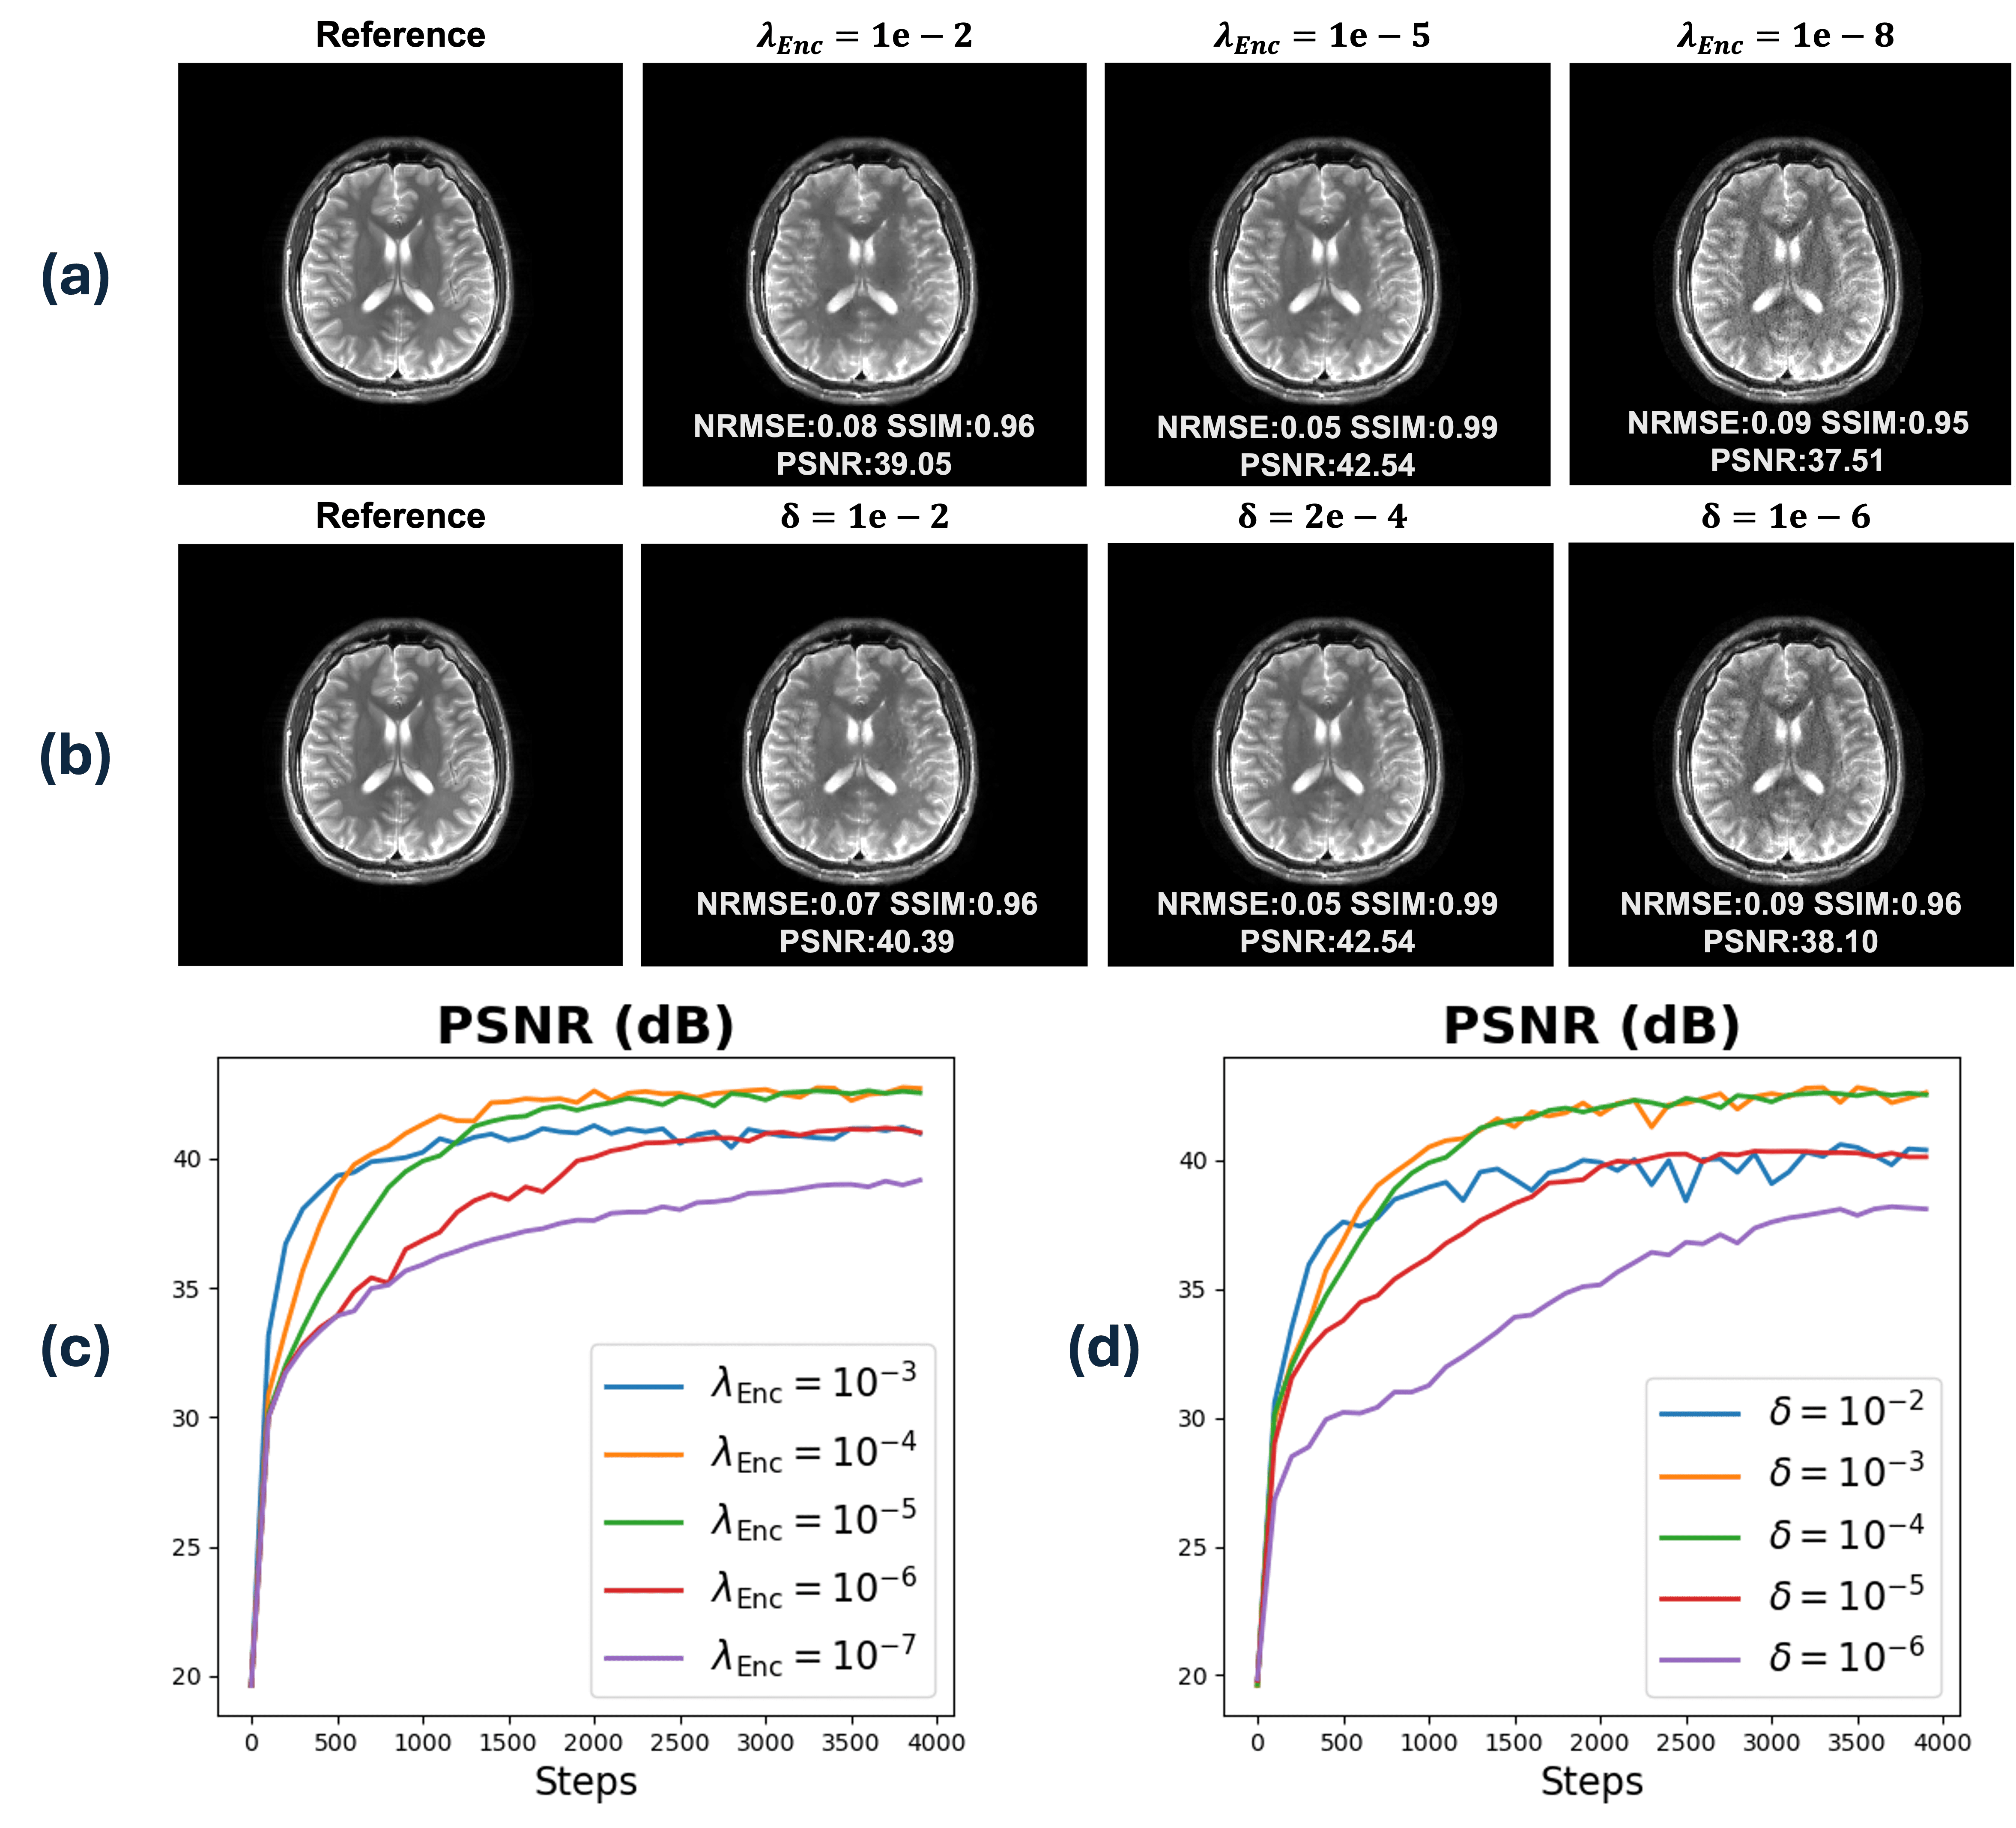

Refer to caption

Figure 7: Illustrating choosing hyperparameter for Bayesian Optimization; (a),(c) 2\ell_{2} regularization strength for Hash Encoder parameters. (b),(d) Self-weighting loss stability value δ\delta that controls the emphasis on higher frequency k-space components.

Fig. 7 demonstrates the impact of optimized hyperparameters in the upper level of (6). The encoder’s 2\ell_{2} regularization strength λEnc\lambda_{\mathrm{Enc}} adjusts the degree of regularization on the positionally encoded feature representation; sub-optimal choices lead to over- or under-regularization. Similarly, the loss-weighting controller δ\delta balances the trade-off between image smoothness and fine details. According to (9), a larger δ\delta diminishes higher-frequency components relative to the lower-frequency terms, resulting in blurrier reconstructions. Conversely, smaller δ\delta emphasizes high-frequency components, producing clearer but potentially more aliased images.